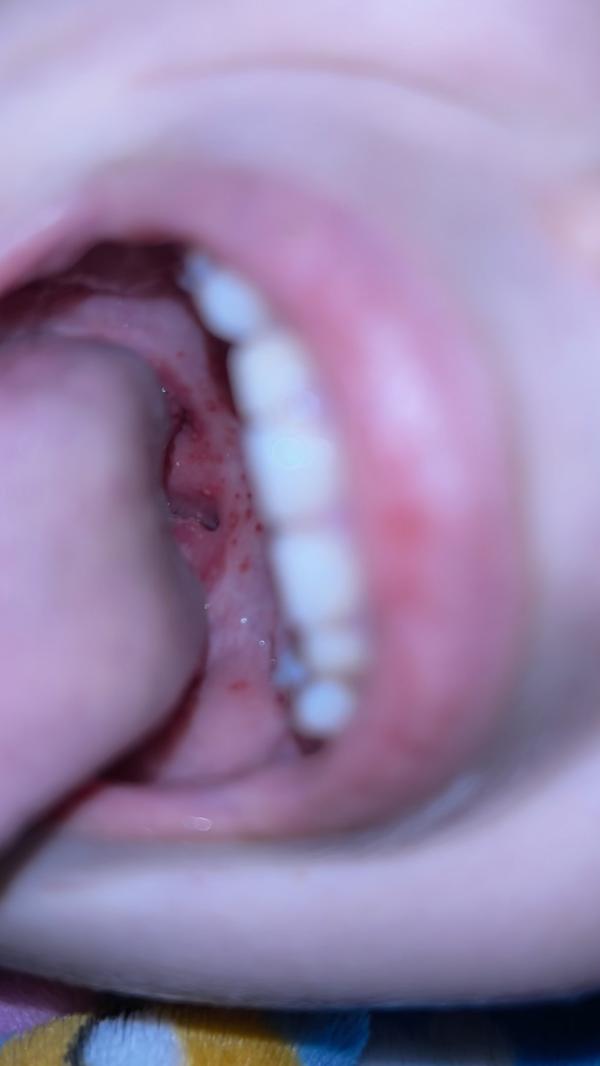

Здравствуй. Девушки, помогите пожалуйста. Чем пшыкать?

Болит бедняжке, не может кушать. Пить тоже больно. Поставили стафилококк инфекцию

Очень похоже как у моих деток стрептокок. Сделайте стрептотест. Когда начала давать аб на второй день стало уходить.

У моей было неделю назад похожая картина в горле, температура 39, не ела почти ничего (

Пили антибиотик через день стало легче